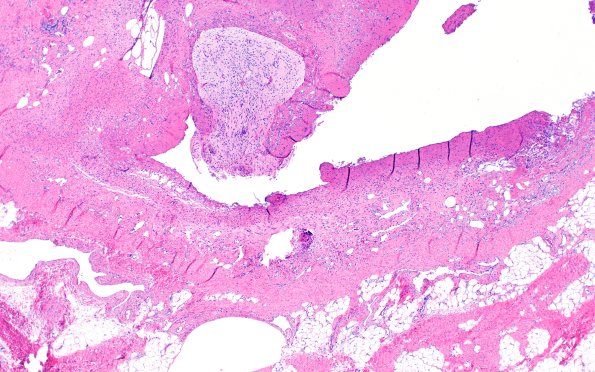

Routine H&E-stained sections of the "parietal cephalocele" show skin and soft tissue with a central lesion consisting of atrophic epidermis with no adnexal structure and underlying soft tissue containing abundant myxoid stroma. Scattered dilated vascular channels are seen. A small fragment of neuroglial tissue is also present. (H&E) ----Comment: Similar appearing lesions have been variously called “sequestrated meningoceles of the scalp” or “hamartoma of the scalp with ectopic meningothelial elements”. However, due to the intracranial malformation adjacent to the lesion, which is not seen in the two aforementioned entities, as well as the presence of heterotopic neuroglial tissue, we favor this to represent a dysraphic malformative process, most consistent with an encephalocele.